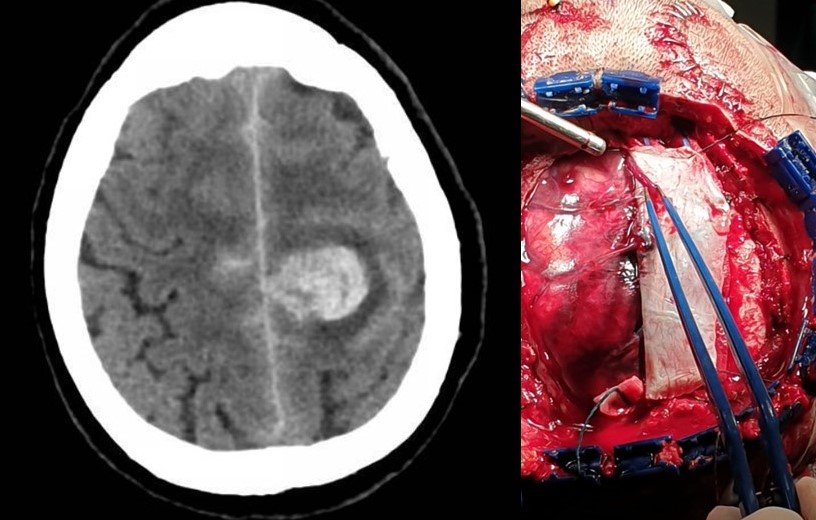

- Malformaciones arteriovenosas (MAVs): Responsables de un 4-5% de las hemorragias subaracnoideas. Están representadas fundamentalmente por las MAV piales, caracterizadas por la presencia de ramas arteriales que dan lugar a un nido malformativo, compuesto por arteriolas y capilares aberrantes, que recibe sangre a alta presión y que drena a través de una o varias venas. Por lo general, se trata de lesiones complejas cuyo tratamiento va a estar condicionado por su tamaño, localización dentro del cerebro y características del drenaje venoso. En caso de que se diagnostiquen previo a su ruptura (generalmente debido a que pueden inducir crisis epilépticas) y midan menos de 3 centímetros, pueden ser tratadas con radiocirugía, si bien en estos casos el efecto del tratamiento se demora unos 2 años. La cirugía por su parte constituye el tratamiento estándar de estas lesiones. Puede tener lugar, al igual que los aneurismas, de forma previa a la ruptura o bien tras producirse ésta. Previo a la cirugía debe considerarse la posibilidad de la embolización de la lesión.